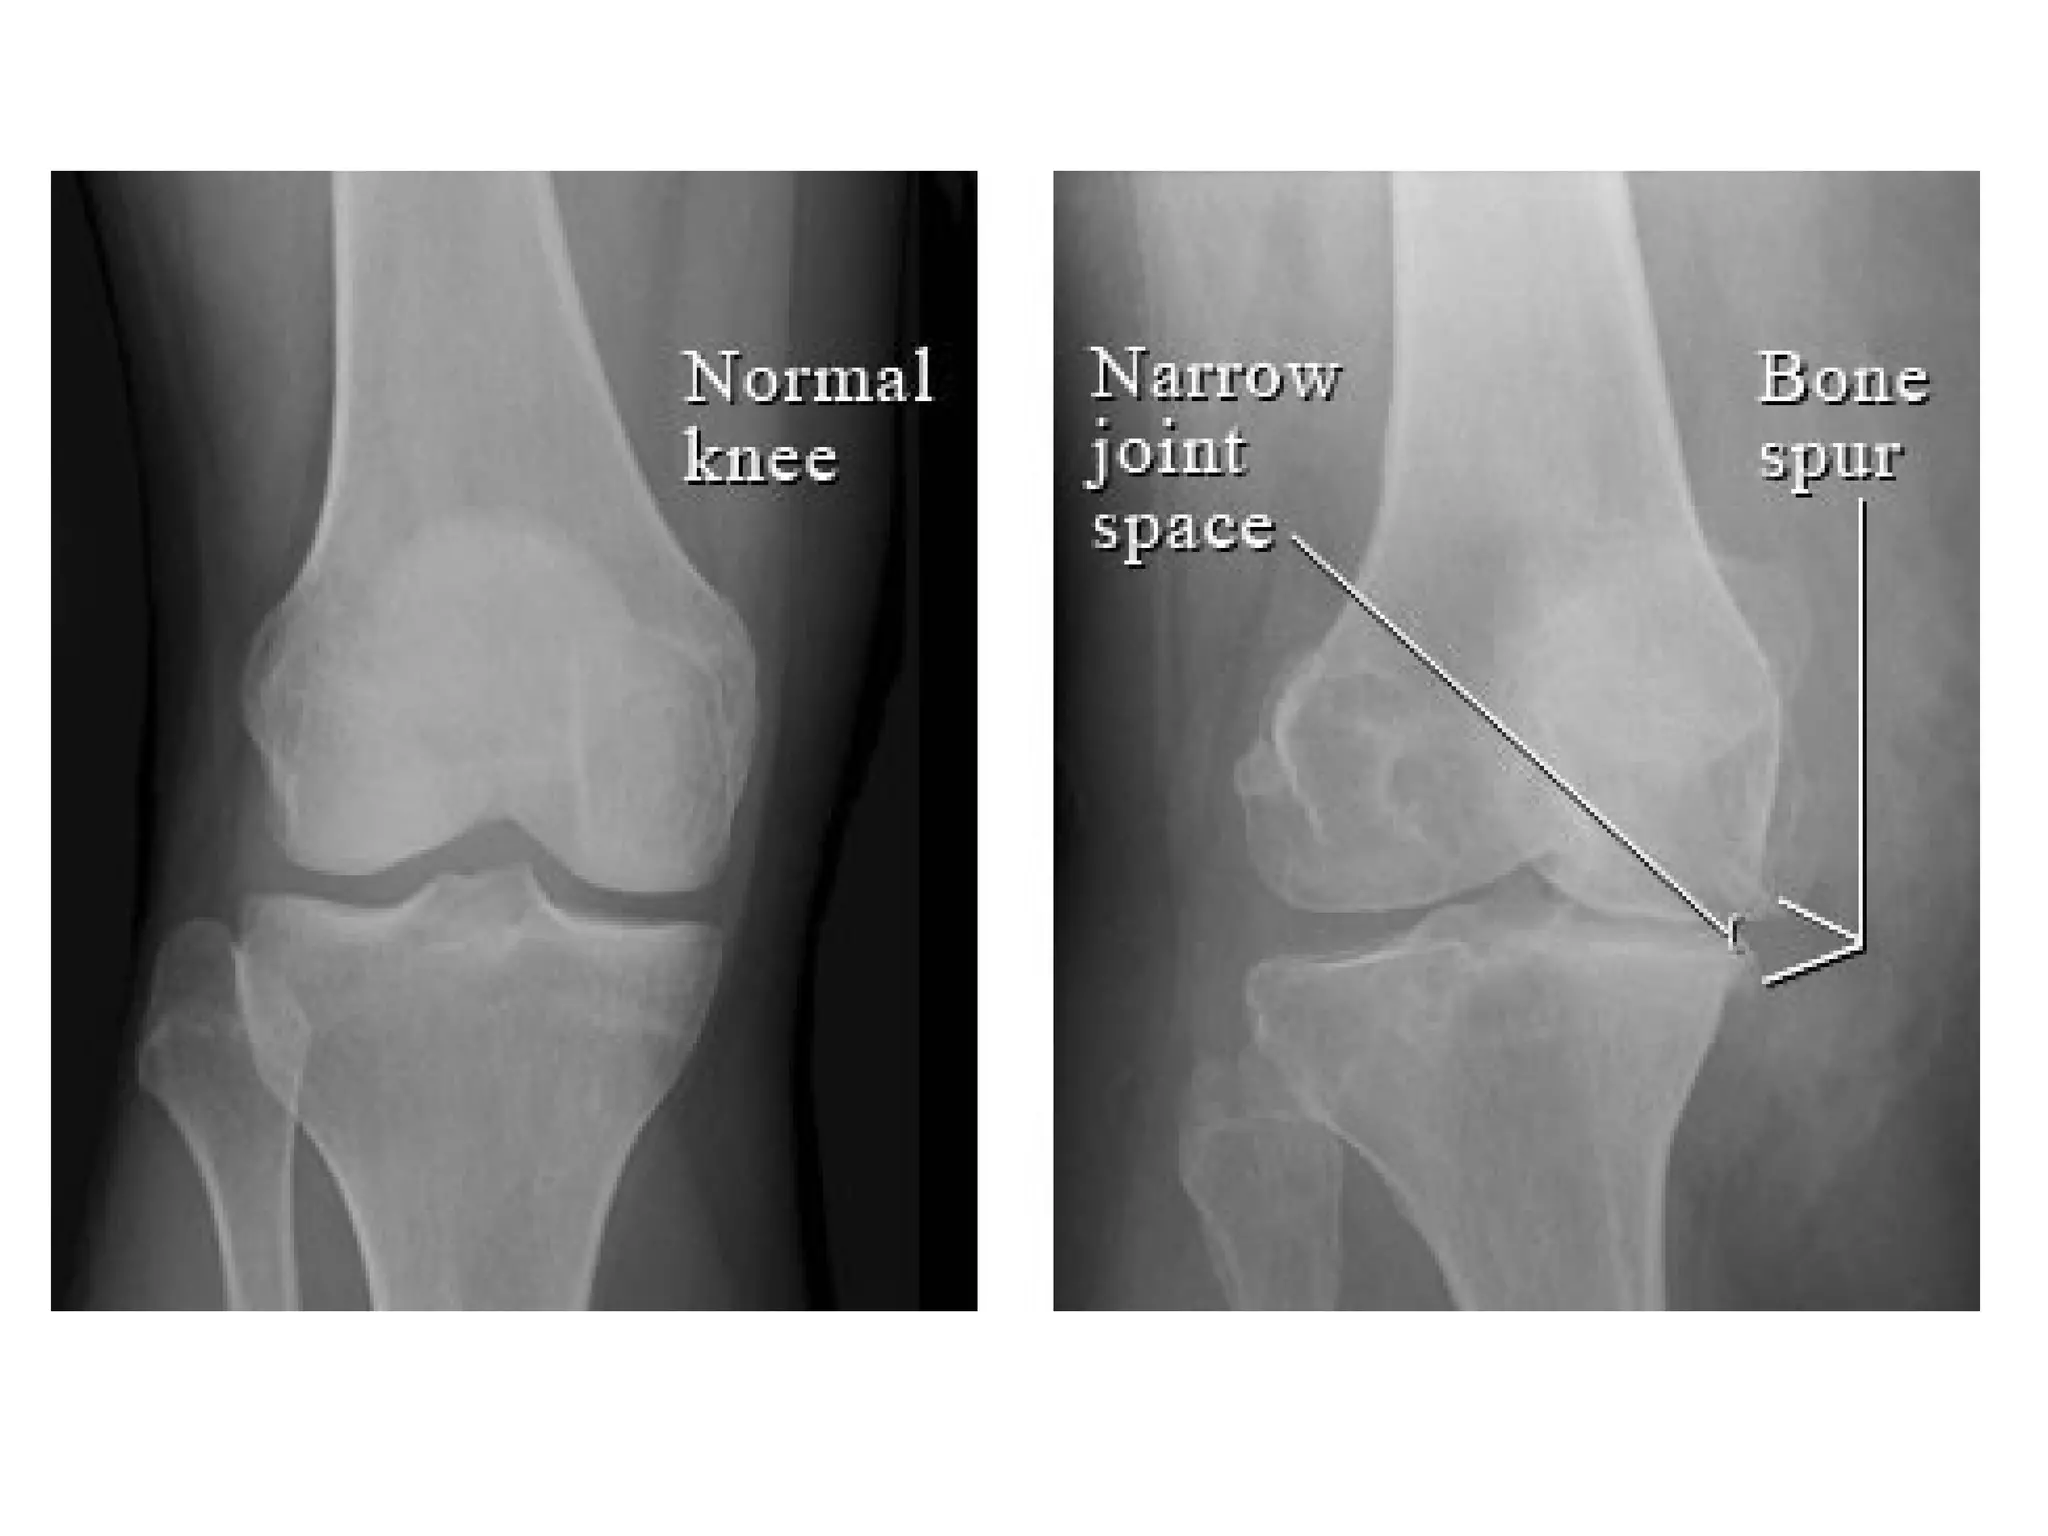

c) Radiographic Features : 5 hallmarks

1-Narrowing of joint space , usually

asymmetrical

2-Subchondral sclerosis

3-Subchondral cysts (Geode) , well-defined

lytic lesion (one of the common differential

diagnoses of a lytic epiphyseal lesions)

4-Osteophytes (bone spur)

5-Lack of osteoporosis

In the knees , primary OA predominately involves the medial tibiofemoral and

patellofemoral compartments , the asymmetric medial joint space loss (white

arrow) causes a varus deformity on standing radiographs , a large

osteophyte classically forms on the medial tibial articular margin (red

arrow) , subchondral sclerosis and cyst formation may also be found